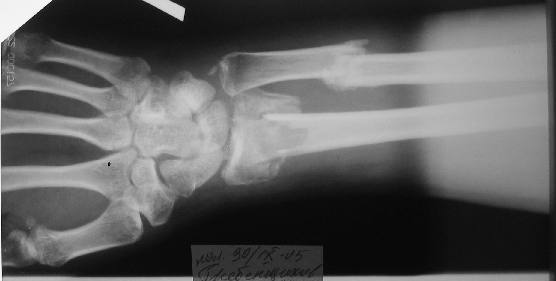

перелом Н/3 предплечья

Больному 27 лет. Травма 2 месяца назад, проводилась закрытая репозиция. Контрольные снимки 3 недели назад (смотреть вложение).

В нашу больницу обратился 2005-10-22.

Планируем провести открытую репозицию фиксацию пластинами.

Обдумываем, как провести репозицию? Предварительно провести дистракцию аппаратом внешней фиксации за нескольких дней до открытой репозиции или во время открытой репозиции?